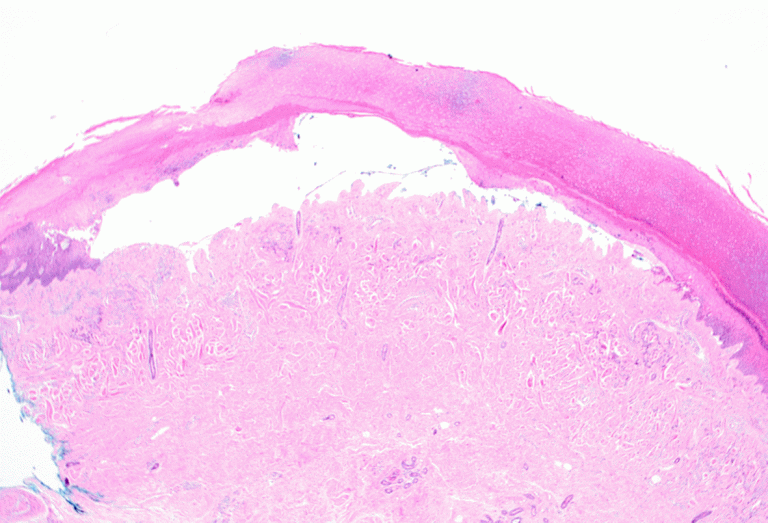

Арьсанд порфирин ихсэн арьсны нөсөөжилт ихсэлтээр илрэх арьсны эмгэг